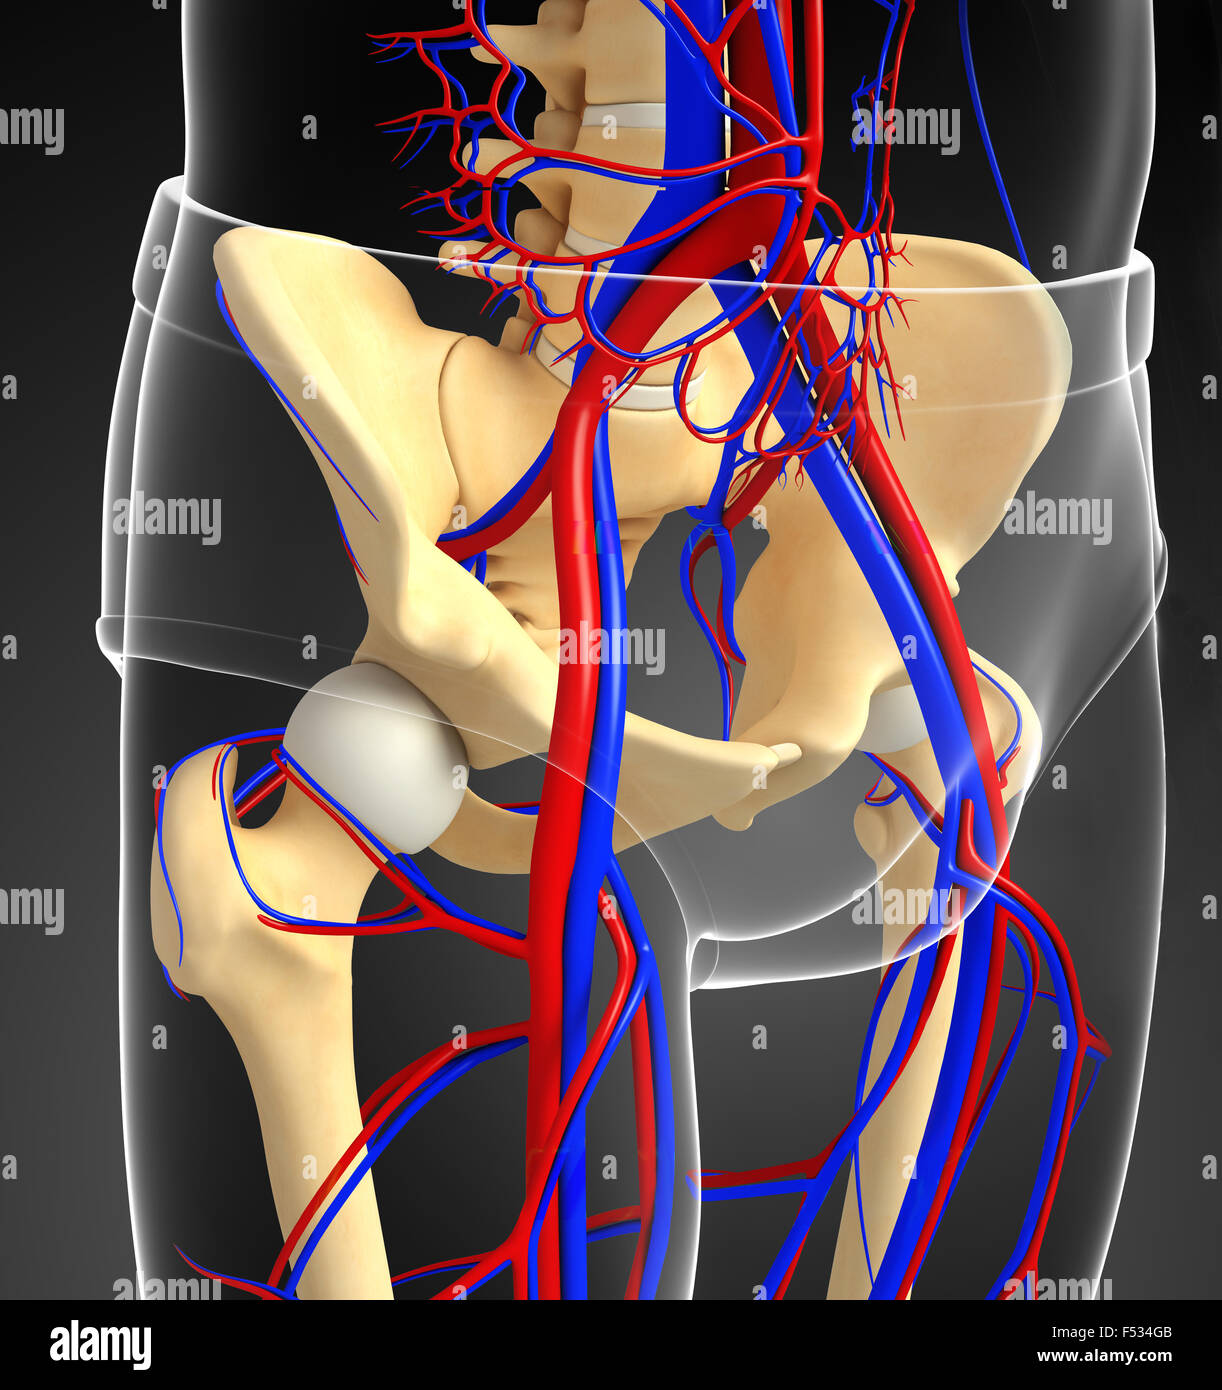

Анатомия человека: кровеносная система и её связь со скелетом